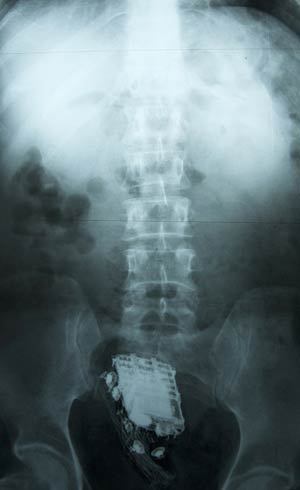

Um prisioneiro do Sri Lanka que tentou esconder seu telefone celular durante uma inspeção em sua cela foi descoberto quando os guardas ouviram toques vindos de suas nádegas, informou um funcionário dos serviços médicos nesta sexta-feira (8).

O condenado de 58 anos de idade precisou ser internado no hospital nacional em Colombo, onde os médicos mais tarde retiraram o aparelho de seu reto.

"O homem tinha escondido o telefone dentro dele mesmo", disse o funcionário, que pediu para não ser identificado.

— Infelizmente para ele, o telefone tocou na hora errada e os guardas sabiam que ele tinha um telefone na extremidade errada.

Ele disse que o homem permaneceu no hospital por dois dias, mas recebeu alta e foi enviado de volta para a prisão nesta sexta-feira (8), depois que o celular foi retirado.